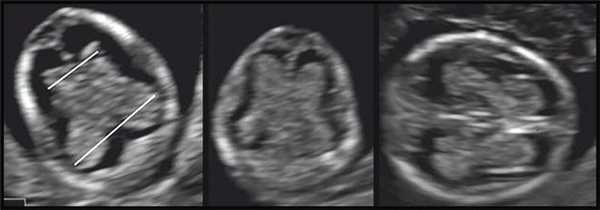

Оценку СС в нашей работе мы проводили визуально (есть или нет правильная картина «бабочки») без проведения измерений параметров. На рис. 3 показан ряд нормальных картин «бабочки» СС боковых желудочков головного мозга плода, полученных при двухмерном ультразвуковом сканировании, в 12-13 нед беременности.

Рис. 3. Отображен ряд нормальных картин «бабочки» СС боковых желудочков головного мозга плода, полученных при двухмерном ультразвуковом сканировании, в 12-13 нед беременности.

На момент исследования КТР составил в среднем 61,4 мм (в пределах 46,3-80,6 мм). На рис. 4 представлены полученные картины СС на стандартном аксиальном срезе на уровне крыши III желудочка во всех исследованных случаях. Отдельно показаны 5 случаев проспективной оценки картины СС боковых желудочков при ОДП плода. Данные КТР и БПР головы плода приведены соответственно для каждого случая на этом же рисунке.

У всех плодов с ОДП при эхографии структур головного мозга было отмечено отсутствие типичной картины «бабочки» СС независимо от уровня их исследования.

Объединяющими характеристиками картины СС при этом были

- Уплощенный (или с некоторой выпуклостью) латеральный контур сплетений с отсутствием характерной для «бабочки» талии посередине.

- Практически одинаковое расстояние между затылочными и лобными порциями.

- Отсутствие картины крыши III желудочка.

По аналогии сравнения нормальной картины СС с «бабочкой» полученные нами характеристики картины СС у плодов с ОДП вызвали у нас ассоциацию с различной формой хитиновых оболочек «тараканов» (см. рис. 4).

Рис. 4. Отображена эхографическая картина аксиального среза СС на уровне крыши III желудочка у всех плодов с ОДП, диагностированными нами в 11-14 нед беременности.

Приведена аналогия с хитиновыми оболочками «тараканов». В последнем ряду показаны случаи проспективной оценки СС при ОДП. В каждом случае приведены копчико-теменной и бипариетальный размеры плода соответственно.